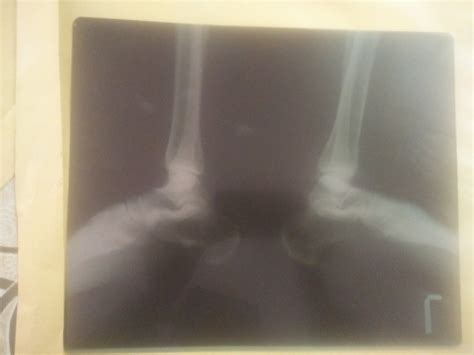

Calcaneal Spur